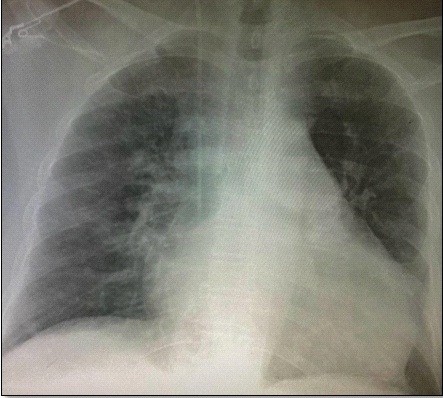

A chest X-ray revealed grade IV cardiomegaly and a cardiothoracic index of 0.62 (Fig. 2). Laboratory tests revealed elevated cardiac biomarkers, with an initial high-sensitivity troponin I of 16.1 ng/dL and creatine phosphokinase MB fraction of 95; the rest of the laboratory results were within normal ranges.

Figure 2. Chest X-RAY. Cardiomegaly with cardiothoracic index of 0.62